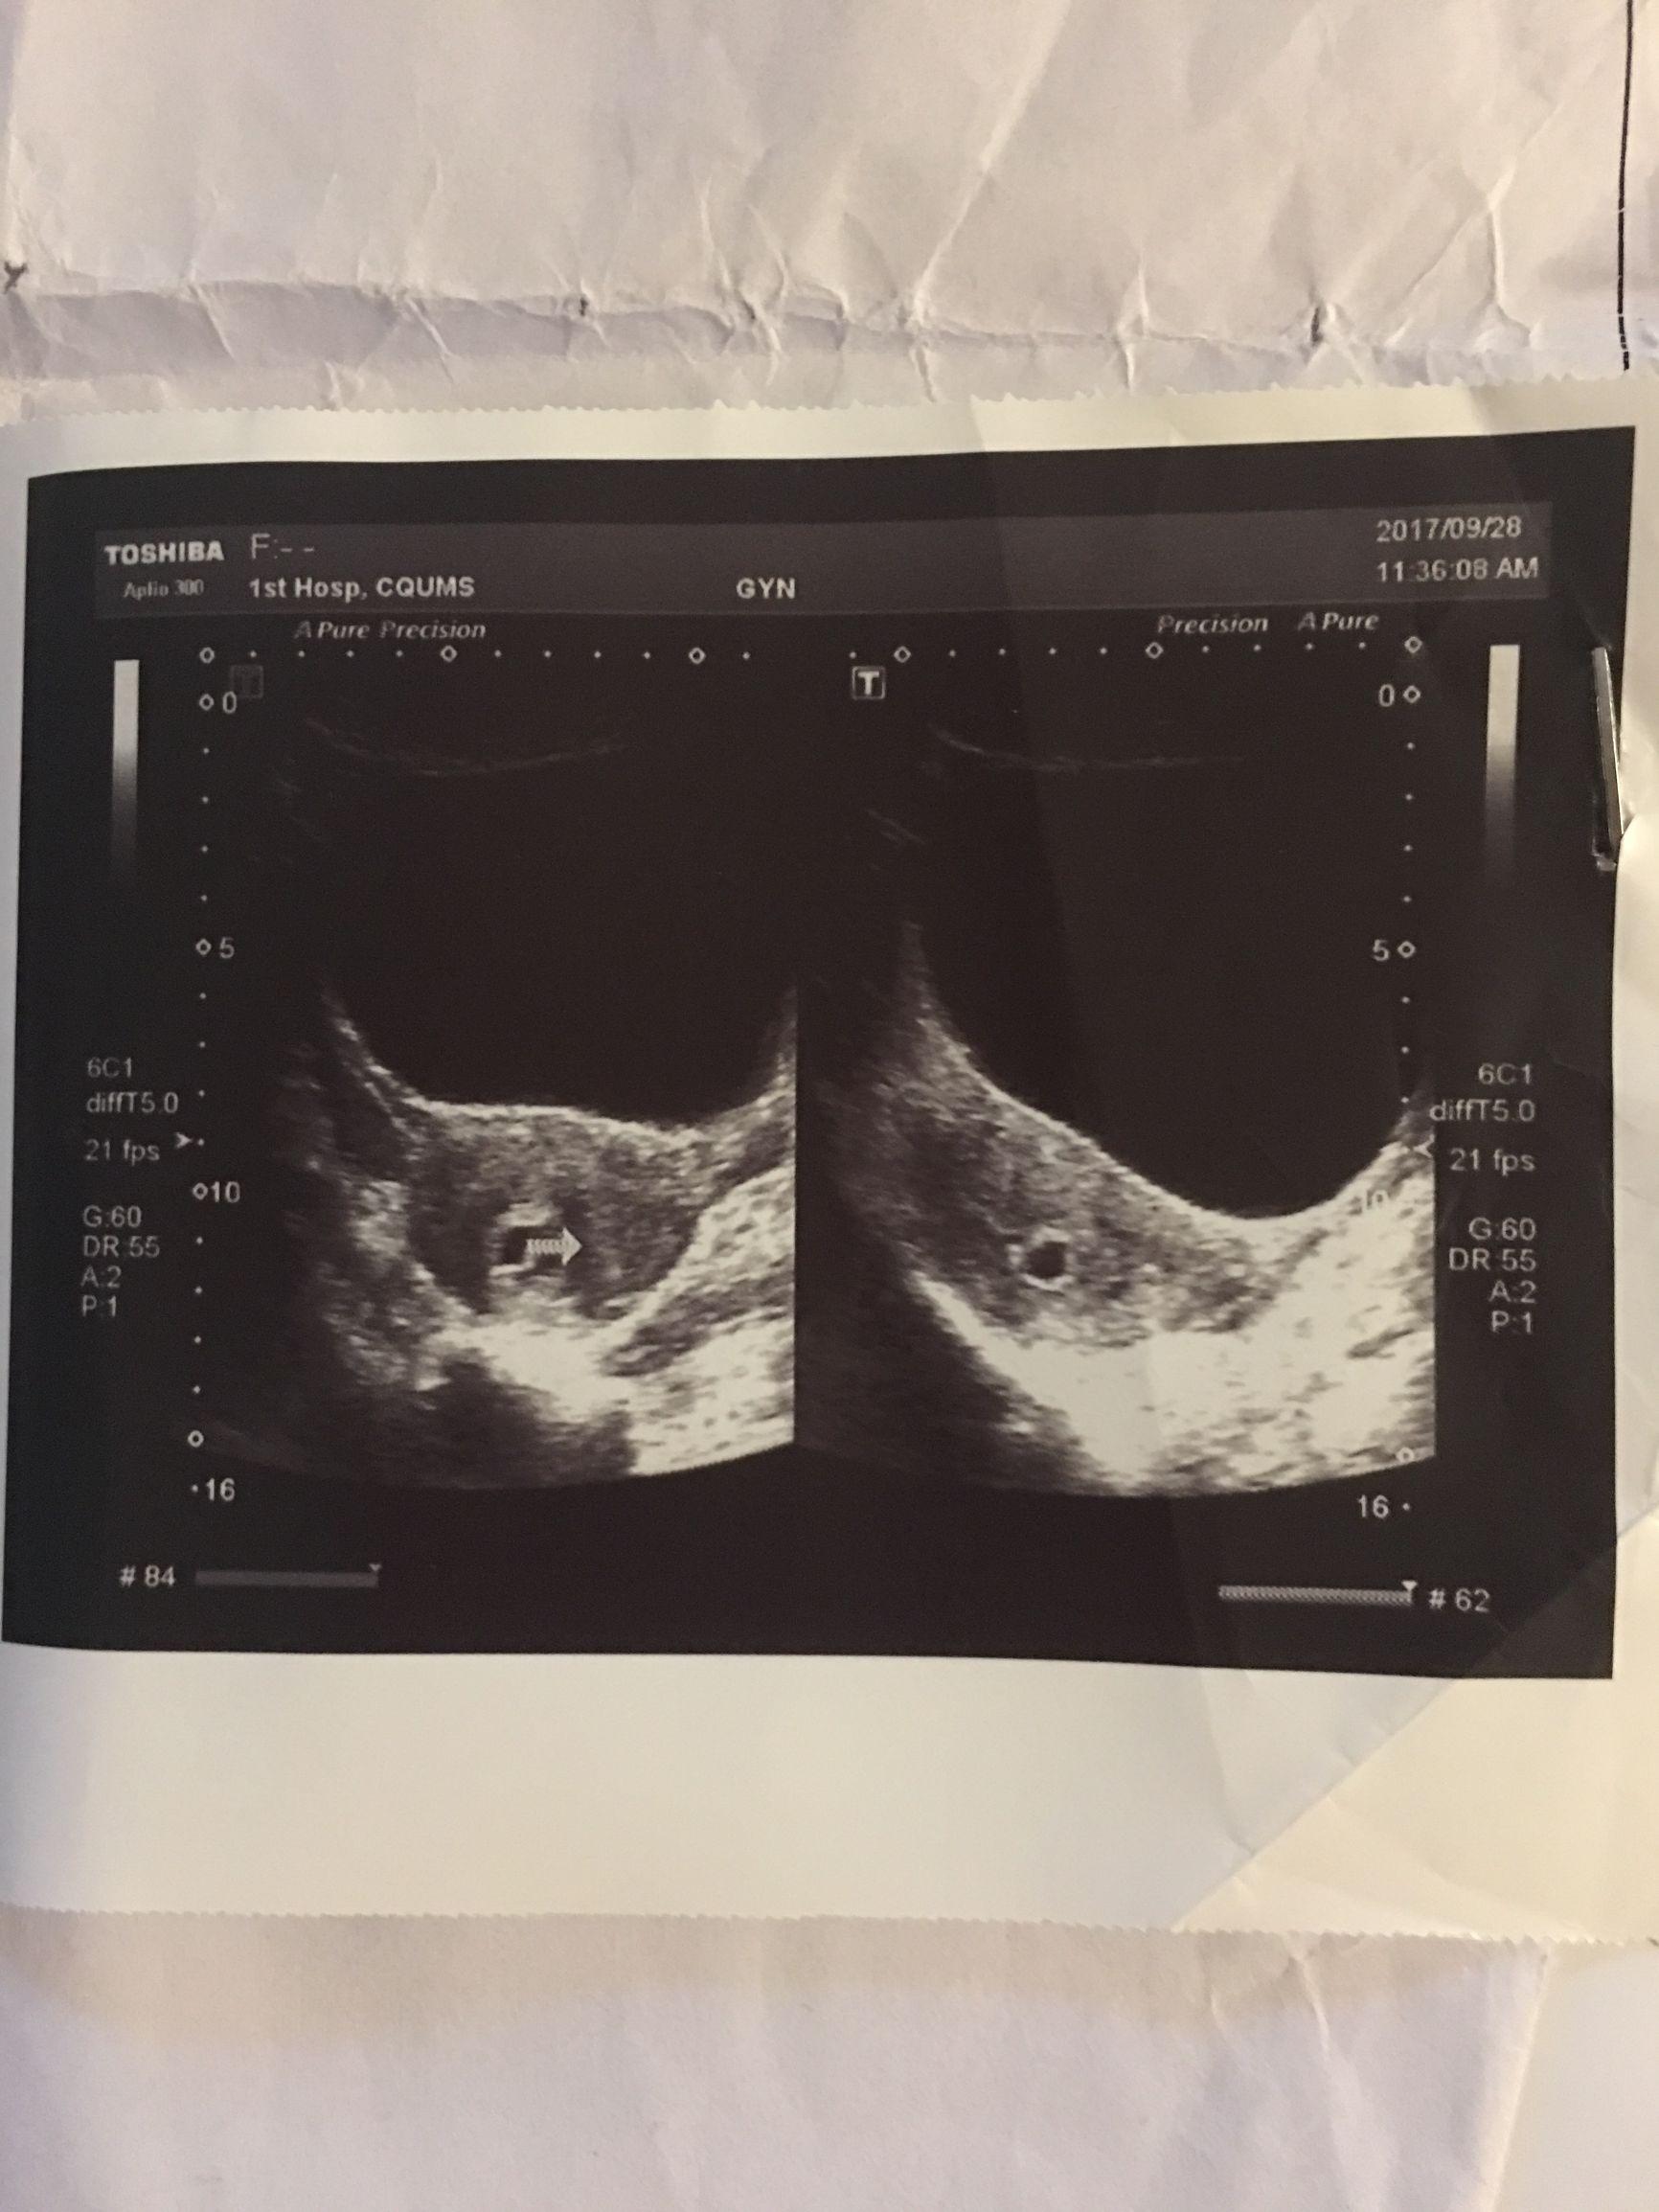

2、復(fù)查B超:藥流后一周,建議女性進(jìn)行B超檢查,以了解子宮內(nèi)是否有殘留物。